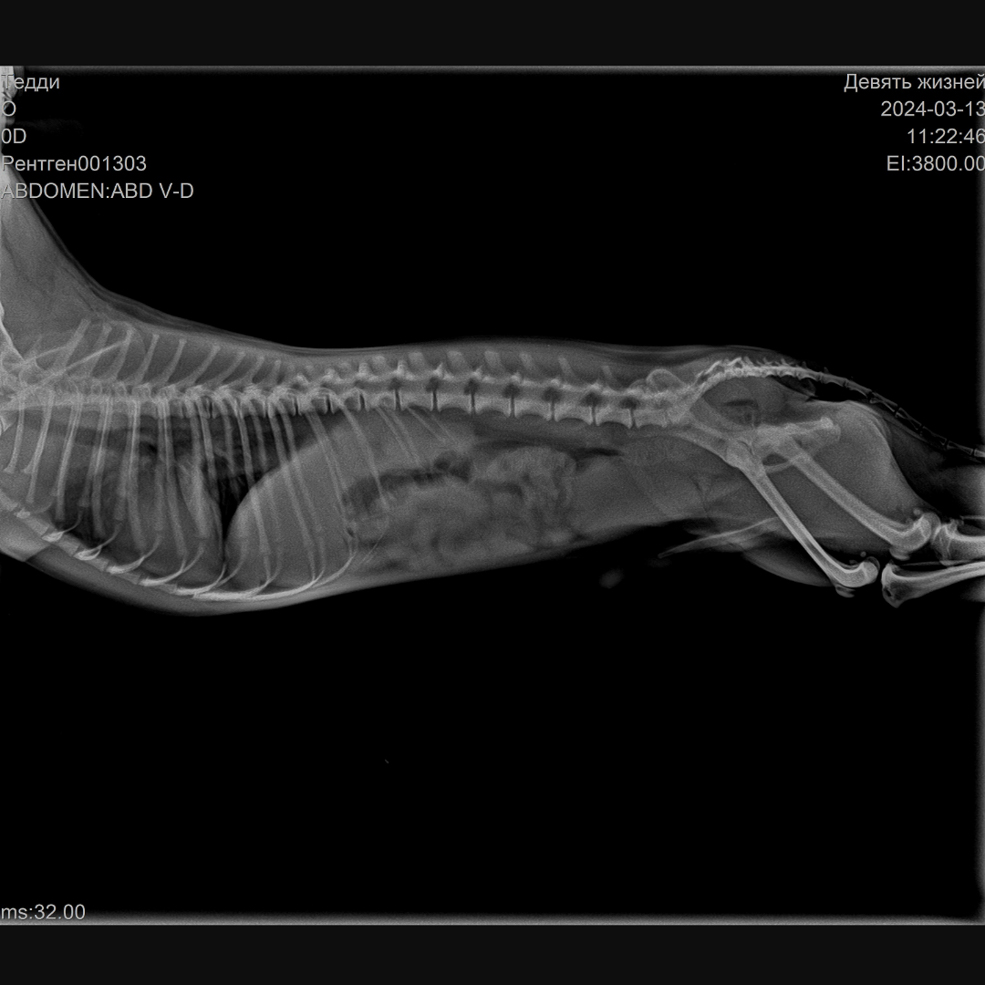

Нас встретил сотрудник Кирилл. Он полностью провёл осмотр, сделал рентген – у них есть вариант электронного снимка, когда можно приближать, рассматривать. Оказалось, что все конечности целые.